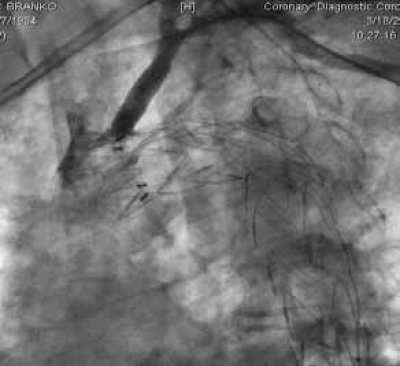

Perkutana transluminalna angioplastika sa stentom zbog aterosklerotične stenoze (90%) desne subklavijalne i desne vertebralne arterije

Dislokacija aterosklerotičnog plaka pri implantaciji aortnog stent grafta, sa stenozom leve zajedničke karotidne arterije u koju je transponirana leva subklavijalna arterija u sklopu hybrid procedure.

Dilatacija orificijuma leve zajedničke arterije sa implantacijom stenta.